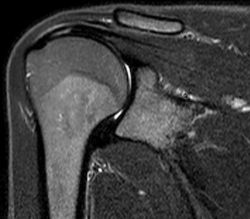

L'IRM

De quoi s'agit-il?

Un gros aimant pour faire des images...